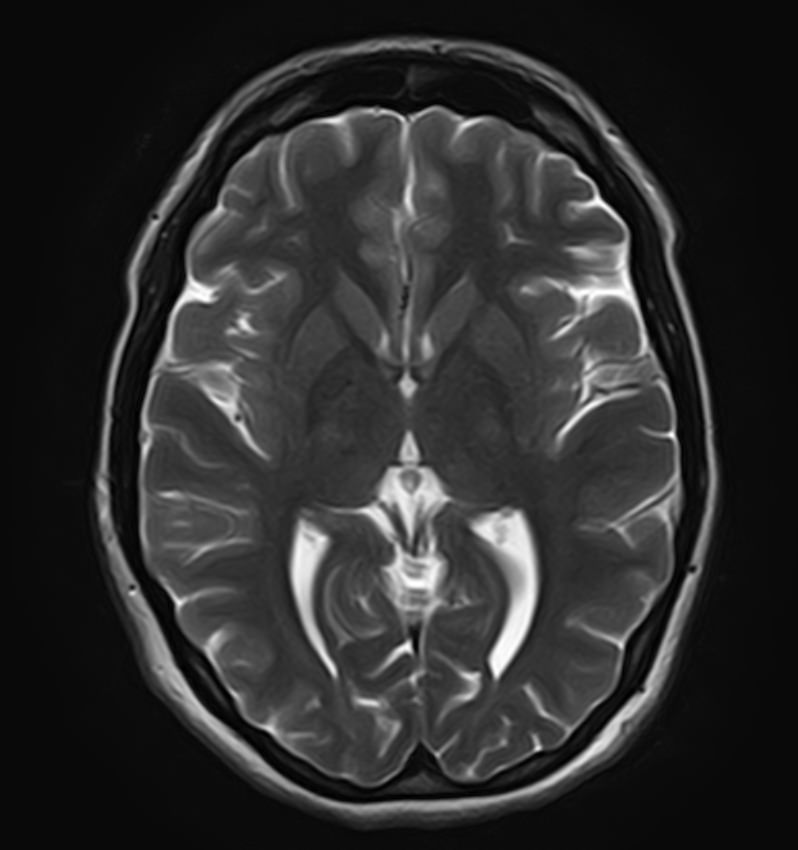

К центральной нервной системе организма относится головной мозг, расположенный в полости черепа, и спинной мозг, проходящий в спинномозговом канале позвоночного столба. В головном мозге находятся высшие центры управления всем организмом, спинной мозг имеет двусторонние связи с ними, то есть является проводником импульсов от периферии к головном мозгу и обратно.

Патология ЦНС может проявляться многообразной неврологической симптоматикой, в зависимости от уровня поражения. Причинами ее появления могут быть травматические повреждения, проникновение инфекции, демиелинизирующие и дегенеративные заболевания, сосудистая патология, опухолевые процессы.

Для диагностики заболеваний ЦНС в клинике «Доступная медицина» проводится комплексное обследование МРТ ЦНС (центральной нервной системы). Клиника укомплектована высокотехнологичным оборудованием, в частности, новейшим 32-канальным высокопольным томографом TOSHIBA VANTAGE TITAN 1,5 Тесла с высокой разрешающей способностью для точной диагностики заболеваний центральной нервной системы.

Комплексное обследование ЦНС выполняется как в стандартном режиме, когда не применяется использование контраста, так и с контрастным усилением. Для более точной диагностики некоторых патологий головного и спинного мозга внутривенно вводится контрастное вещество. С помощью контраста можно обнаружить опухолевые образования размером от 1 мм, демиелинизирующие процессы, дегенеративно-дистрофические заболевания, воспалительные процессы, сосудистую патологию.